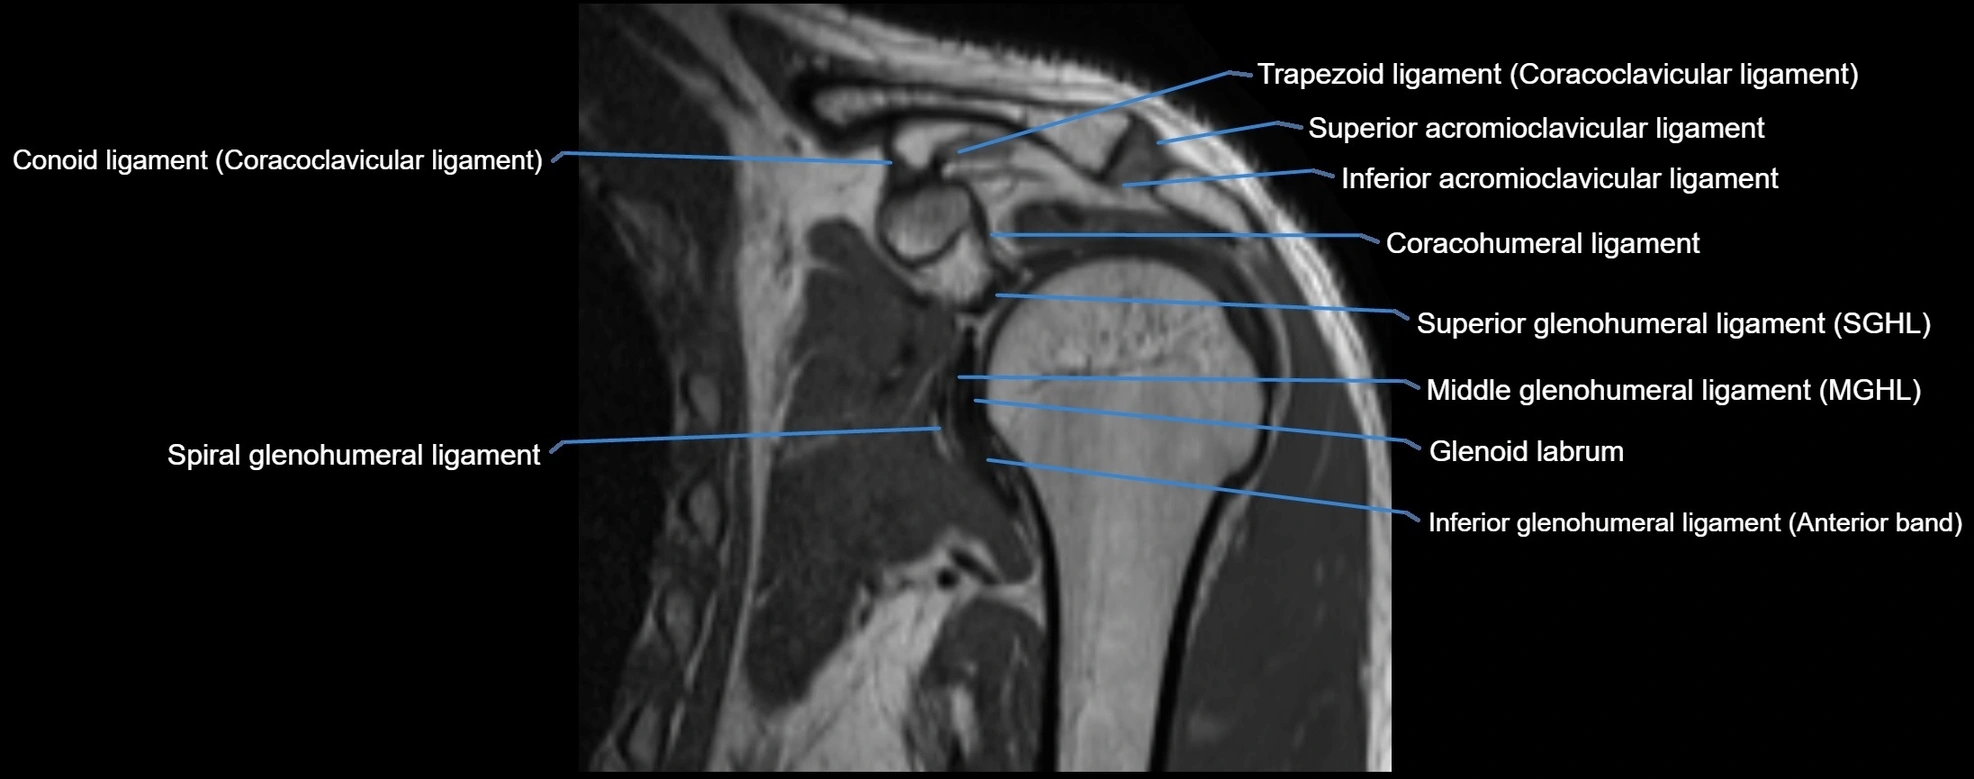

MRI Appearance

• T1-weighted images:

• Normal ligament: Low signal (dark linear band) spanning acromion to clavicle.

• T2-weighted images:

• Normal ligament: Low signal, homogeneous.

• Proton Density Fat-Saturated (PD FS):

• Normal ligament: Low signal, uniform thickness.

• Partial tear or sprain: Bright signal or contour irregularity.

• Complete tear: Clear discontinuity with bright signal gap and joint effusion.

• Excellent for assessing joint capsule, coracoclavicular ligaments, and periarticular edema.

MRI images

image